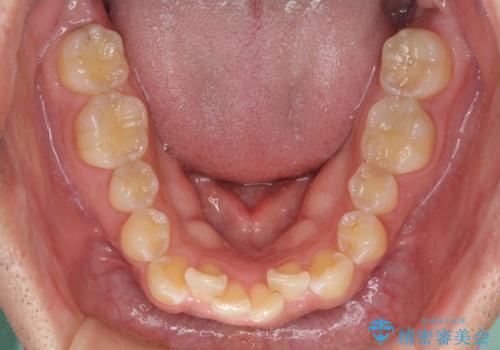

ディープバイトと叢生を解消 インビザライン矯正

- 前歯のデコボコを強い咬みしめを気にして来院された患者様です。

インビザラインを用いて、前歯の叢生を解消するとともに、ディープバイトを改善していくこととしました。